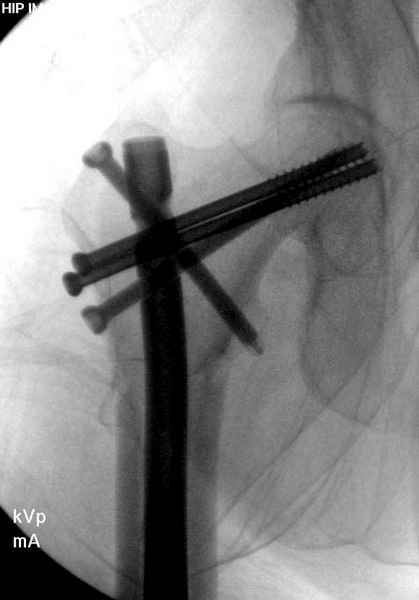

Профилактику дальнейшего раскола неполного перелома шейки провели тремя канюлированными шурупами.

На второй день после выписки упал дома. Снимки приложены. Коллеги рекомендуют удаление шурупа и вытяжение. Что делать?

Правильно, ситуация изменилась, как говорят у нас теперь "different animal", надо решать проблему подвертельного перелома. При наличии различных вариантов фиксаторов, включая Страйкер Гамма 3, мы выбрали DePuy Antegrade Trachanteric Nail из-за многовариантности проксимальной фиксации и двойного изгиба. Вводится через вертел под 8 градусным углом, и есть достаточный передний диафизарный изгиб, предупреждающий пенетрацию дистального переднего кортекса.